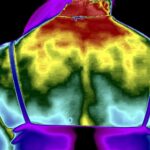

Como no caso do termograma abaixo de um paciente do sexo masculino, 55 anos, sem comorbidades e que apresentou dor lombar ao caminhar e não possuía nenhum exame de imagem prévio. Foi realizado uma Análise Termofuncional e detectado alterações térmicas condizentes com o relato de dor.

Dentro do estudo da Termofuncional foi possível analisar e determinar a disfunção do paciente, fechando o diagnóstico e programando todo o tratamento.